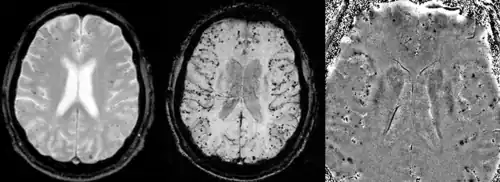

Cerebral amyloid angiopathy can be presented with lobar intracerebral hemorrhage or microbleeds in the brain. The bleeding usually occurs on the surfaces of the brain in contrast with intracranial haemorrhage due to high blood pressure which occurs in deep locations of the brain such as basal ganglia and pons. In lobar intracerebral bleed, computed tomography (CT) scan would show hyperdense haemorrhage area and hypodense odema around the haemorrhagic site.[27]

MRI sequence of gradient echo and susceptibility weighted imaging (SWI) are useful in detecting microbleeds and deposition of iron on the brain cortex (cortical superficial siderosis).[27] Other MRI indicators of CAA include white matter hyperintensities and cortical thinning.[33]